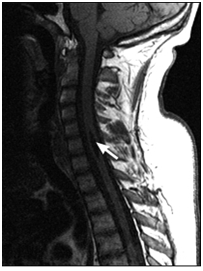

Súlyos trauma a nyaki gerinc: a törés-zavar a C5 csigolya test, súlyos tömörítés az agytörzs, jeleivel gerincvelő-ödéma, a teljes gerinccsatorna szűkület szintjén a törés. MR kép prevertebrális vérömleny.

T1VI T2VI (keverjük) T2VI